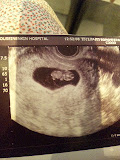

九週二日

今9週2日でした。

心拍もあり一安心。

ただ、血が混じったようなオリモノがあり、運動や力仕事、杏奈の抱っこもなるべく控えるように!ということでした。

予定日は11月6日だけど、帝王切開だから10月終わりの38週に出産になるみたい。